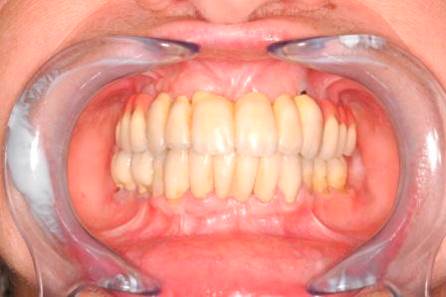

Bezzubá čelist je hlavní indikací pro ošetření pomocí implantátů. Zejména celkové zubní náhrady v dolní čelisti mají velice nízkou stabilitu a držení díky velkému úbytku kosti.

S pomocí zubních implantátů můžeme díky různým kotevním systémům (třmeny, kulové hlavy, Locatory) zajistit stabilitu a držení protézy nebo při použití většího počtu implantátů zhotovit pevné náhrady – můstky nalepené nebo našroubované na pevno na implantáty.

S těmito typy náhrad můžeme dosáhnout perfektní funkci, výbornou estetiku, fonetiku a současně zajistit u pacienta možnost dobré hygienickou péče a čištění, která je pro životnost implantátů velice důležitá.